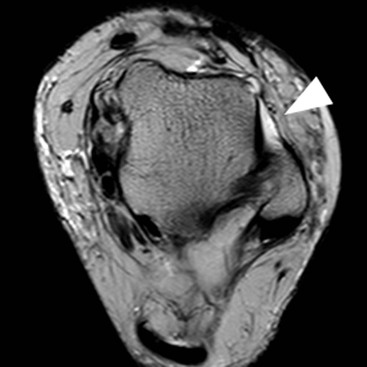

Patellar tendinopathy involving the proximal tendon attachment is commonly referred to as ‘jumper’s knee’ because of its association with athletic activities that involve jumping. It can be demonstrated on MRI and ultrasound where it typically appears as focal thickening of the central deep portion of the proximal tendon with increased Doppler vascularity (Fig. 46-52). On ultrasound the tendinopathic tendon shows low reflectivity and on MRI increased intrasubstance signal. Patellar tendinopathy may also involve the more distal tendon. Osgood–Schlatter disease is a common condition in children aged between 8 and 13 years and is characterised by distal patellar tendinopathy, tibial tubercle enlargement or fragmentation and thickening of the overlying soft tissues. The condition is thought to result from repetitive traction injury related to sporting activity. Tears of the patella or quadriceps tendons may occur, typically on the background of tendinopathy. They are readily evaluated with ultrasound or MRI.